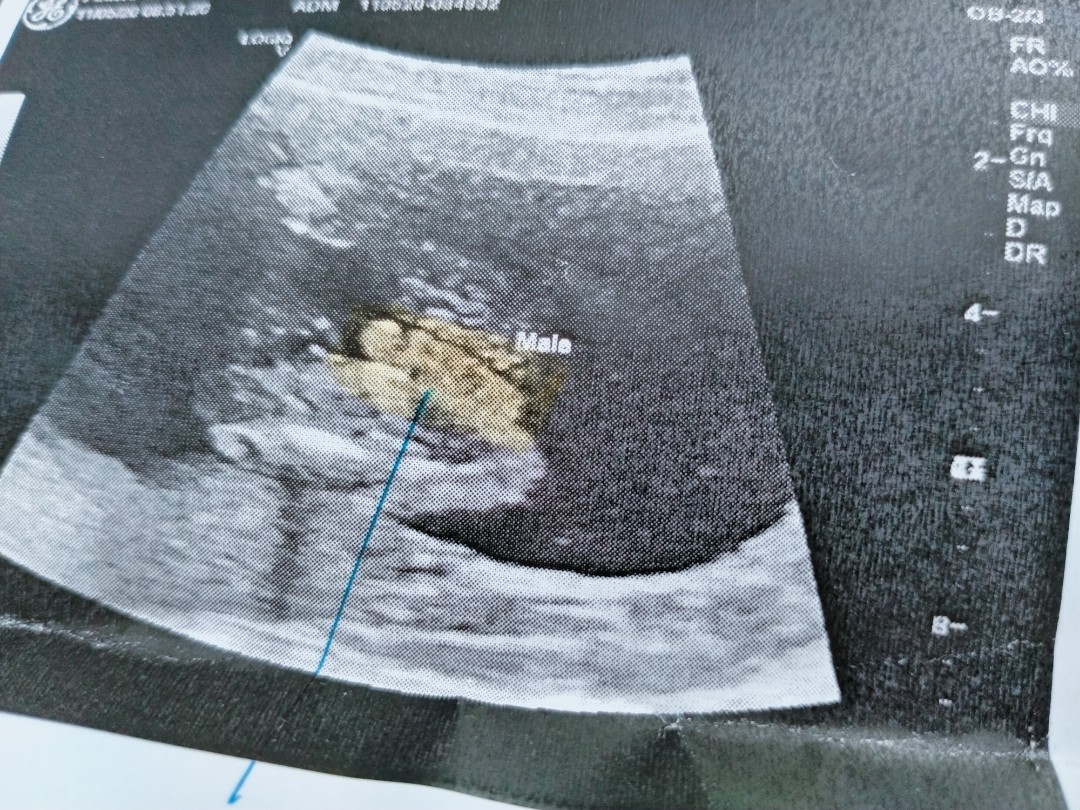

ใบอัลตร้าซาวด์

แม่ๆช่วยดูหน่อยคะ ผช.ใช่ไหมคะ หมอบอก ผช. บ้านไหนได้ ผช. ลงรูปใบซาวด์ให้ดูหน่อยคะ

ชายค่ะ

ผช. ค่ะ

ผ.ช ค่ะ

ผช. จ้า

ผช ค่ะ

ผช.จ้า

ผช.ค่ะ

ผชจ้า

ผช.คะ